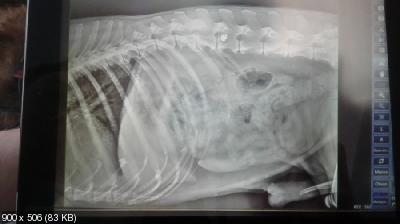

Пес обследован врачем.

Кровь ОАК и Биохимия в пределах показателей, сердце и легкие послушали в норме, по рентгену - задние лапы без изменений, передние - запущенный артроз плечевых суставов, в позвоночнике пуля, перелома по снимкам не обнаружено.

Когти начали врастать в подушечки-пострижены. Запущены зубы-гнилые и сильный запах, нужно будет лечить после курса обезболивающих и противоартрозных препаратов и соответствующее кормление.